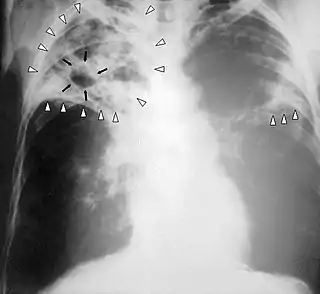

Radiografía de tórax

La radiografía es esencial en el diagnóstico de la enfermedad. Las lesiones típicas radiológicas son apicales, en hemitórax derecho, en segmentos posteriores y en general forman cavidades.

La herramienta para el diagnóstico de caso de tuberculosis es la bacteriología (baciloscopía y cultivo) por su alta especificidad, sensibilidad y valor predictivo. En aquellas situaciones donde los estudios bacteriológicos no sean concluyentes será necesario realizar el seguimiento diagnóstico de acuerdo con la organización de la red de servicios de salud, utilizando otros criterios: clínico, epidemiológico, diagnóstico por imágenes, inmunológico, anatomopatológico.